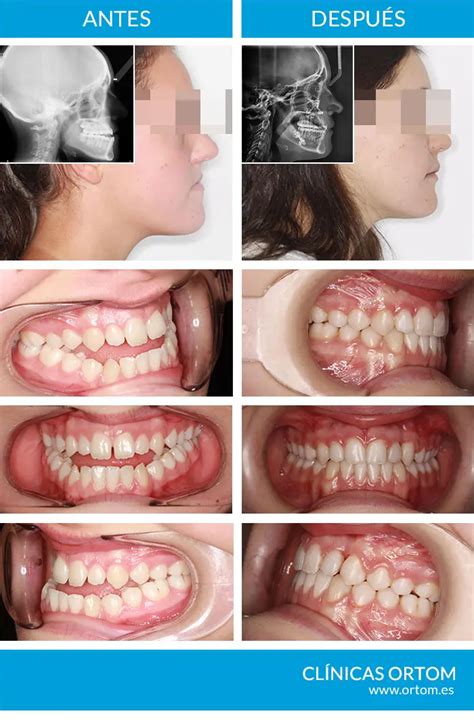

- Anomalías dentofaciales y oclusión dental defectuosa: La maloclusión u oclusión dental defectuosa se refiere a la falta de armonía entre en maxilar superior y la mandíbula. Esta puede ocasionar graves problemas de funcionalidad y estéticos dependiendo de la magnitud y el tipo. Anomalías en la estructura facial por poseer una mandíbula muy grande o por un maxilar pequeño y asimetría en el mentón y la mandíbula son algunas de las consecuencias de la oclusión. También puede generar desgaste y pérdida de piezas dentales, dificultades para masticar y otras afecciones. Este tipo de anomalías se corrigen mediante la cirugía ortognática. Este es un procedimiento que se realiza bajo anestesia general. Es importante que esta intervención la realice un cirujano maxilofacial. Aunque es posible que deba trabajar en conjunto con un especialista en ortodoncia. De esta forma se corregirá la posición de los huesos maxilares y a su vez la forma de la dentadura. La cirugía consiste en realizar una serie de incisiones por la parte interna de la boca. Y reubicar los maxilares. Aunque a veces es necesario cortar parte del hueso. Después, la mandíbula o maxilar es fijado en el lugar mediante tornillos. Este tipo de cirugía puede llegar a ser compleja y el tiempo de recuperación del paciente es de aproximadamente un mes. Pero los resultados suelen ser muy satisfactorios.

La cirugía ortognática corrige la posición de los huesos maxilares.